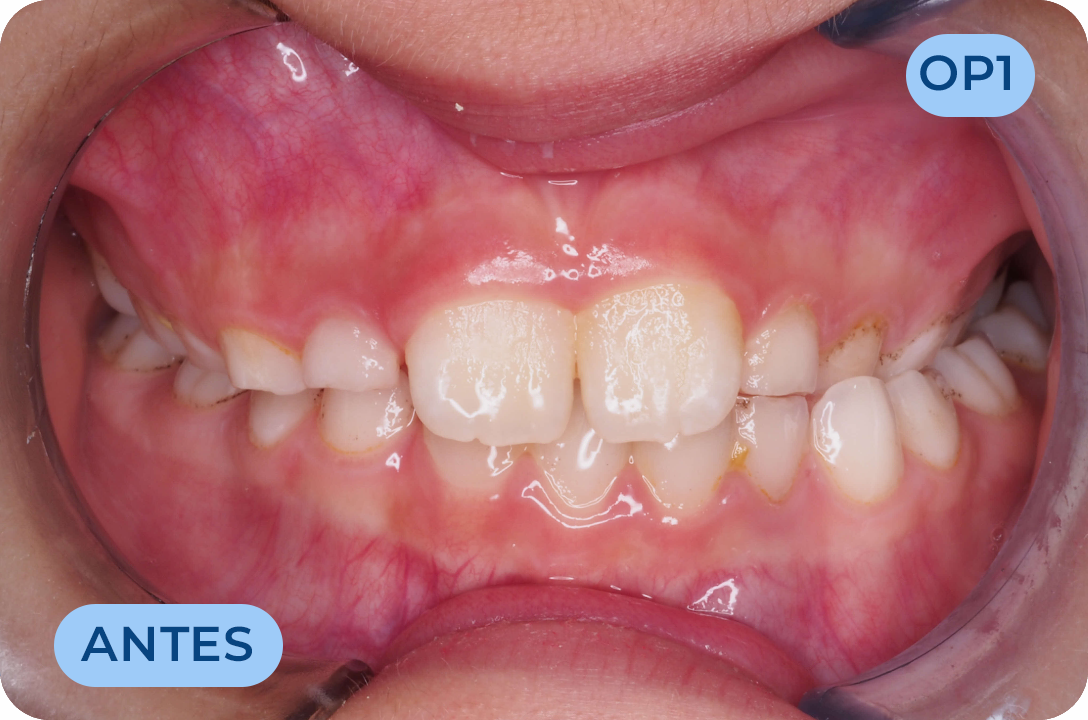

Ortodontia

É a especialidade da Medicina Dentária que se debruça sobre o estudo e correção das más posições dentárias e dos maxilares. Atualmente é possível tratar pacientes de todas as idades, no entanto a 1ª consulta deve ser realizada ainda na infância para intercetar eventuais problemas de desenvolvimento esquelético e funcional.

Odontologia Miofuncional

É a filosofia de tratamento que atua na reeducação da musculatura facial e mastigatória, corrigindo os maus hábitos miofuncionais como a respiração oral, deglutição atípica e posicionamento incorreto da língua, que não sendo resolvidos resultam em deformidades esqueléticas, dentárias e funcionais graves para a saúde geral do indivíduo. O sistema myobrace desempenha um papel importante nesta área.

Odontopediatria

Especialidade da Medicina Dentária dedicada à manutenção da saúde oral dos bebés, crianças e adolescentes. Uma dentição definitiva saudável começa na infância com a prevenção e cultivo de hábitos saudáveis. Temos profissionais com formação específica na área, preparados com a tecnologia adequada para facilitar a consulta. Como a saúde do bebé começa antes do nascimento, todas as mães devem ser aconselhadas em relação aos cuidados antes e após o parto, na consulta de odontologia pré-natal que temos disponível na nossa clinica.